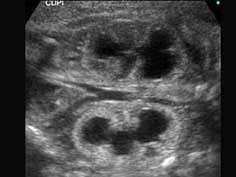

问题 如图为孕34周的胎儿声像图表现,根据图像特点,最可能诊断为 ( )

选项 A、肾畸形 B、以上均不是 C、肾积水 D、肾囊肿 E、多囊肾

答案 C